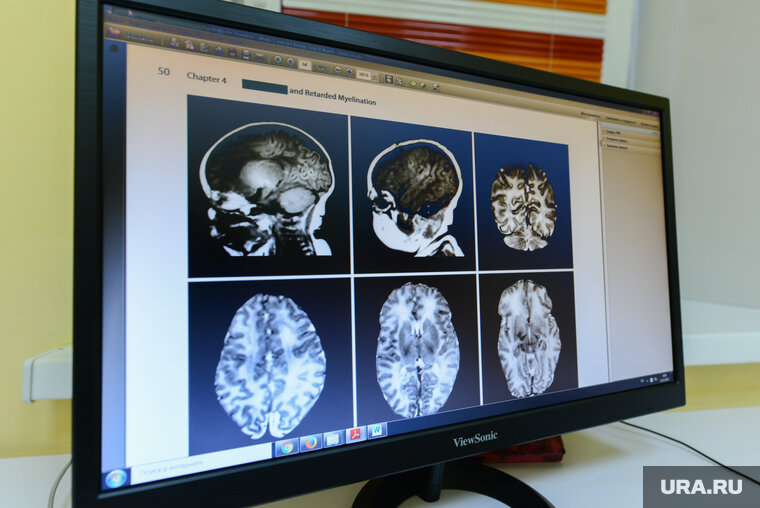

Ребенку провели томографию и выявили перелом черепа

Ночью ребенок плохо спал и плакал, поэтому мать снова вызвала врачей, его госпитализировали. Малышу сделали томографию и обнаружили закрытую черепно-мозговую травму — перелом теменной кости. Сейчас ему стало лучше, маленький пациент начал бегать по палате. Семья пострадавшего малыша благополучная.